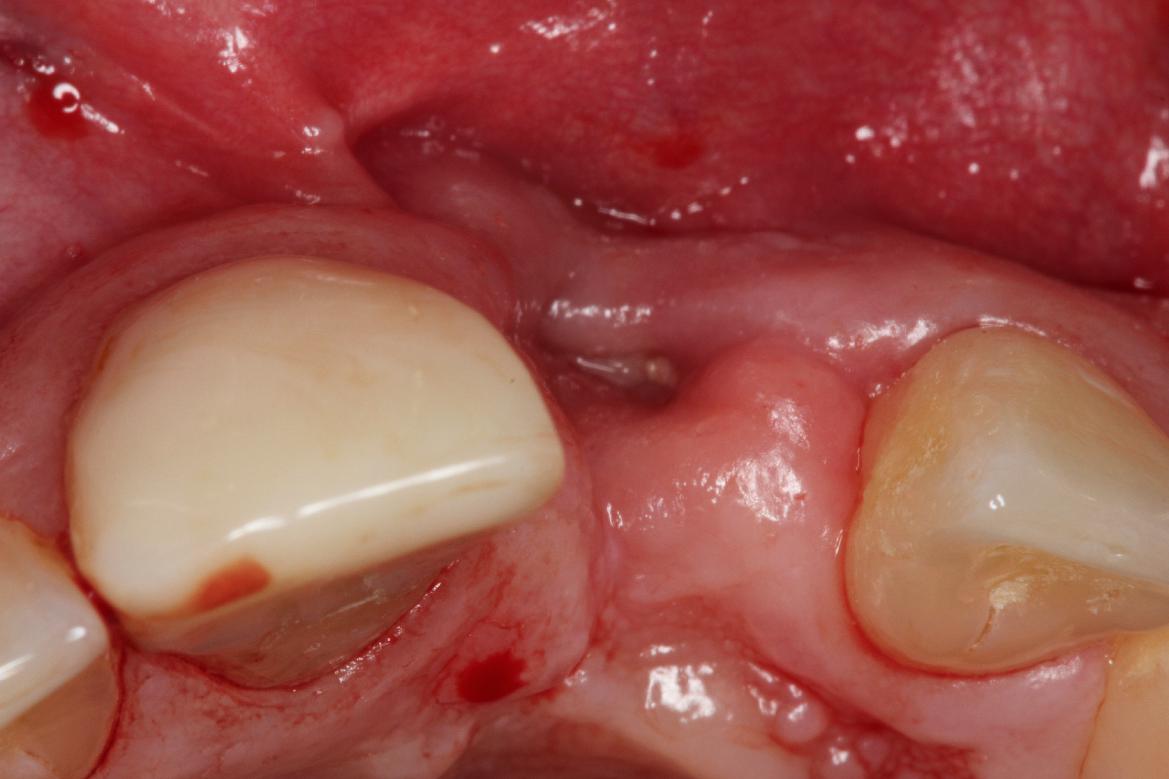

Longitudinal fracture on the root resected tooth 21 with visible buccal fistula